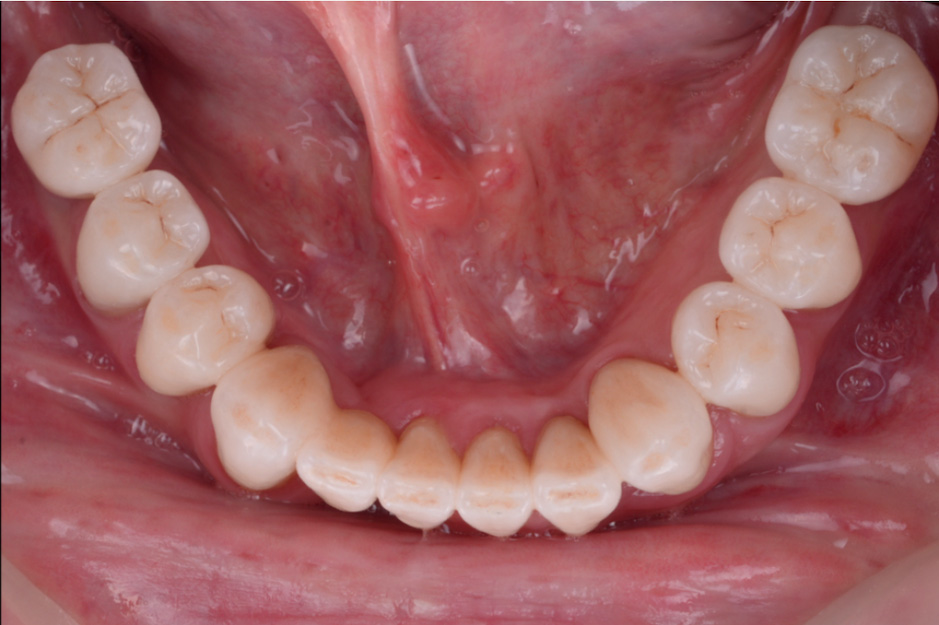

治療前

治療後